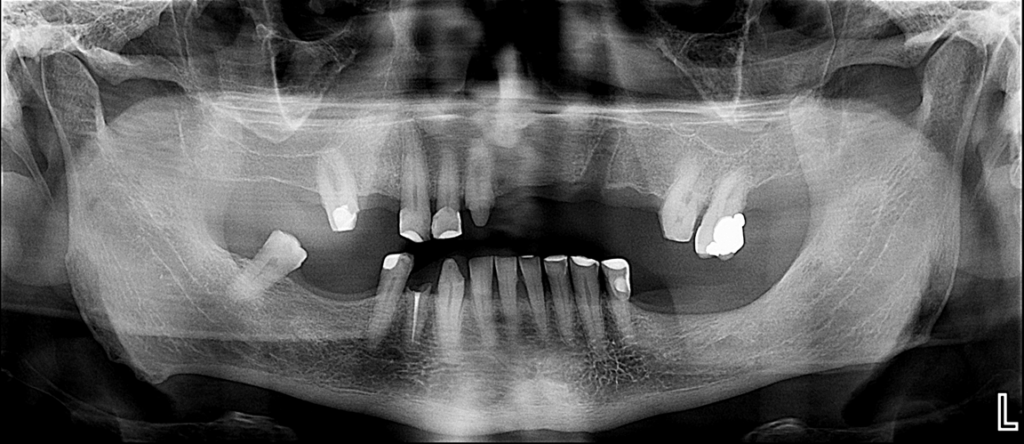

Paciente masculino de 70 años acude con motivo de consulta “evaluación general de la cavidad oral”, se procede a la observación y evaluación de la radiografía panorámica en la que se observa el aplanamiento bilateral de los contornos condilares, la neumatización de ambos senos maxilares, la reabsorción ósea del proceso alveolar, múltiples restauraciones coronarias y tallados coronario, así como la pieza 44 que presenta perdida de estructura coronaria total y obturación de conductos. La pieza 11 presenta una imagen radiolucida a nivel de tercio medio radicular y la pieza 27 una restauración amplia.

Radiografia Panorámica

A la evaluación de la tomografía cone beam de campo mediano (FOV = 10 x 10) se observa en la pieza 11 la presencia de una imagen hipodensa de forma irregular localizada a niel de tercio medio radicular y que se compromete la dentina radicular por mesial y palatino, asimismo se observa la pieza 27 que además de la restauración presenta una imagen hipodensa en raíz palatina a nivel de tercio medio radicular y finalmente un trazo de fractura vertical por distal que compromete la zona de furcación y ocasiona un proceso osteolítico interradicular.

- Reabsorción radicular externa de pieza 11 y de raíz palatina de pieza 27.